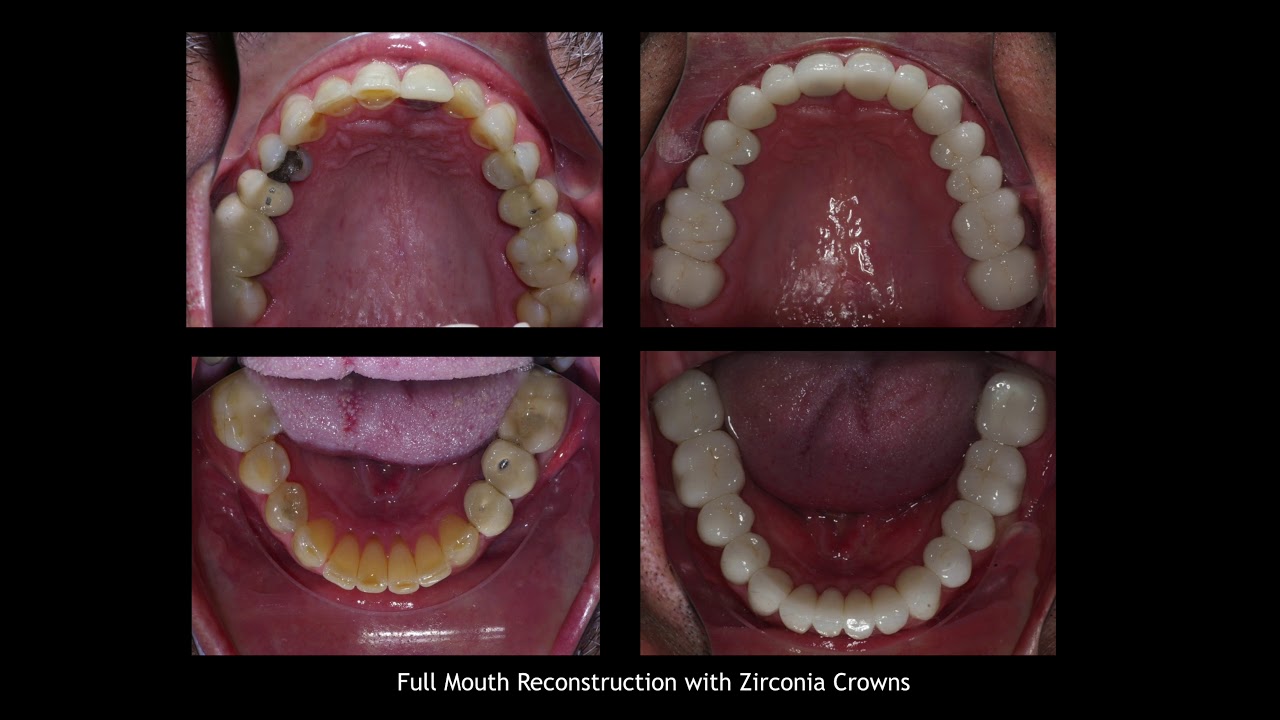

Crown Makeover

Dental crowns are used in smile makeovers to cover teeth that are:

- Stained

- Chipped

- Cracked

- Misshapen

The Best Reconstruction that Lasts the Longest

Everyone considering a full mouth smile makeover (or dental function rehab) of course wants the best that modern dentistry has to offer with an outcome that lasts a long time. Dental implants, crowns, bridges, and veneers can last for years. With proper care and good oral health habits, premium products endure surprisingly well.

The adjacent picture shows the actual crowns and veneer products that were used to alter the biting surfaces of nearly every tooth in the lower jaw as a means for addressing the patient’s crossbite issue.